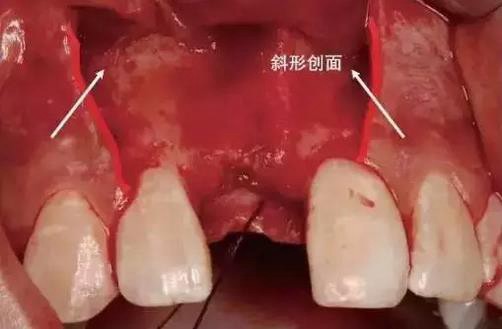

第三步:行縱向切口,從齦溝底向齦緣運(yùn)刀,避開牙齦乳頭,止于軸面角,形成外斜切口(圖)。

齦溝內(nèi)切口與縱向切口

縱向切口應(yīng)做成斜形創(chuàng)面(斜面向外)